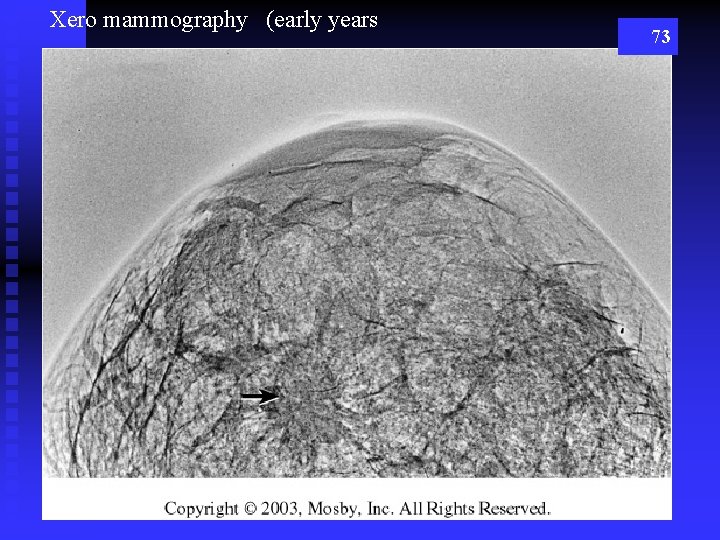

Xero mammography (early years 73